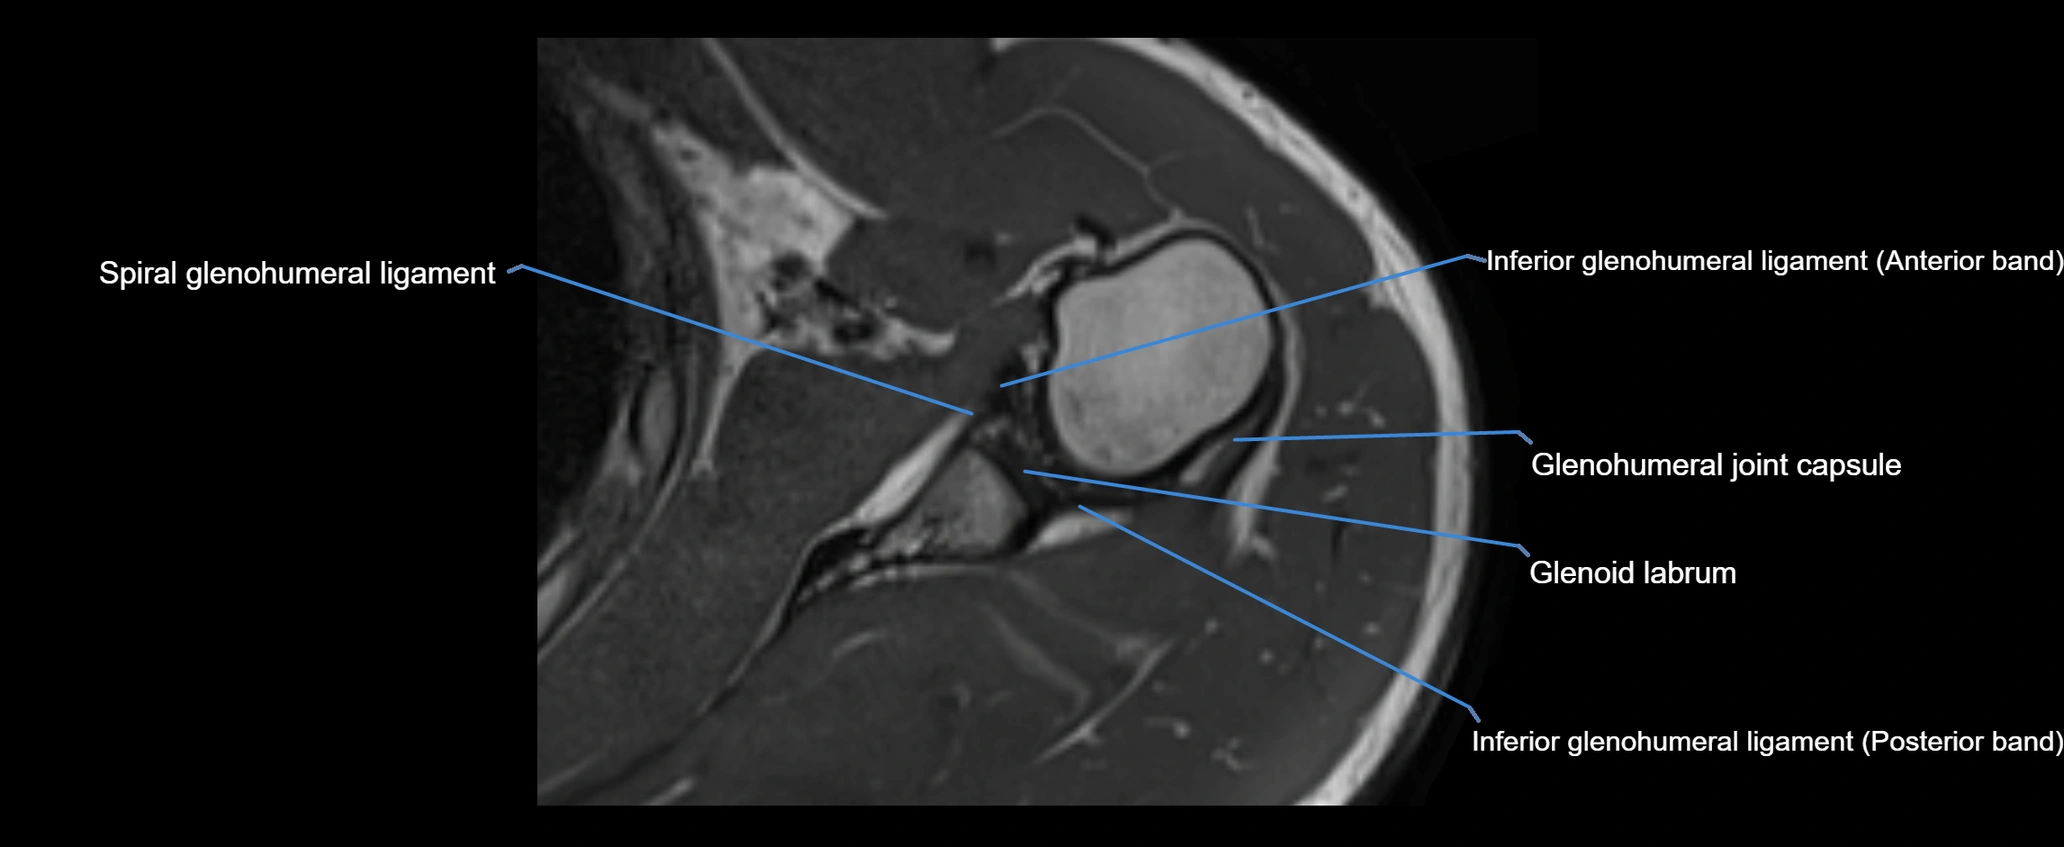

MRI images

image